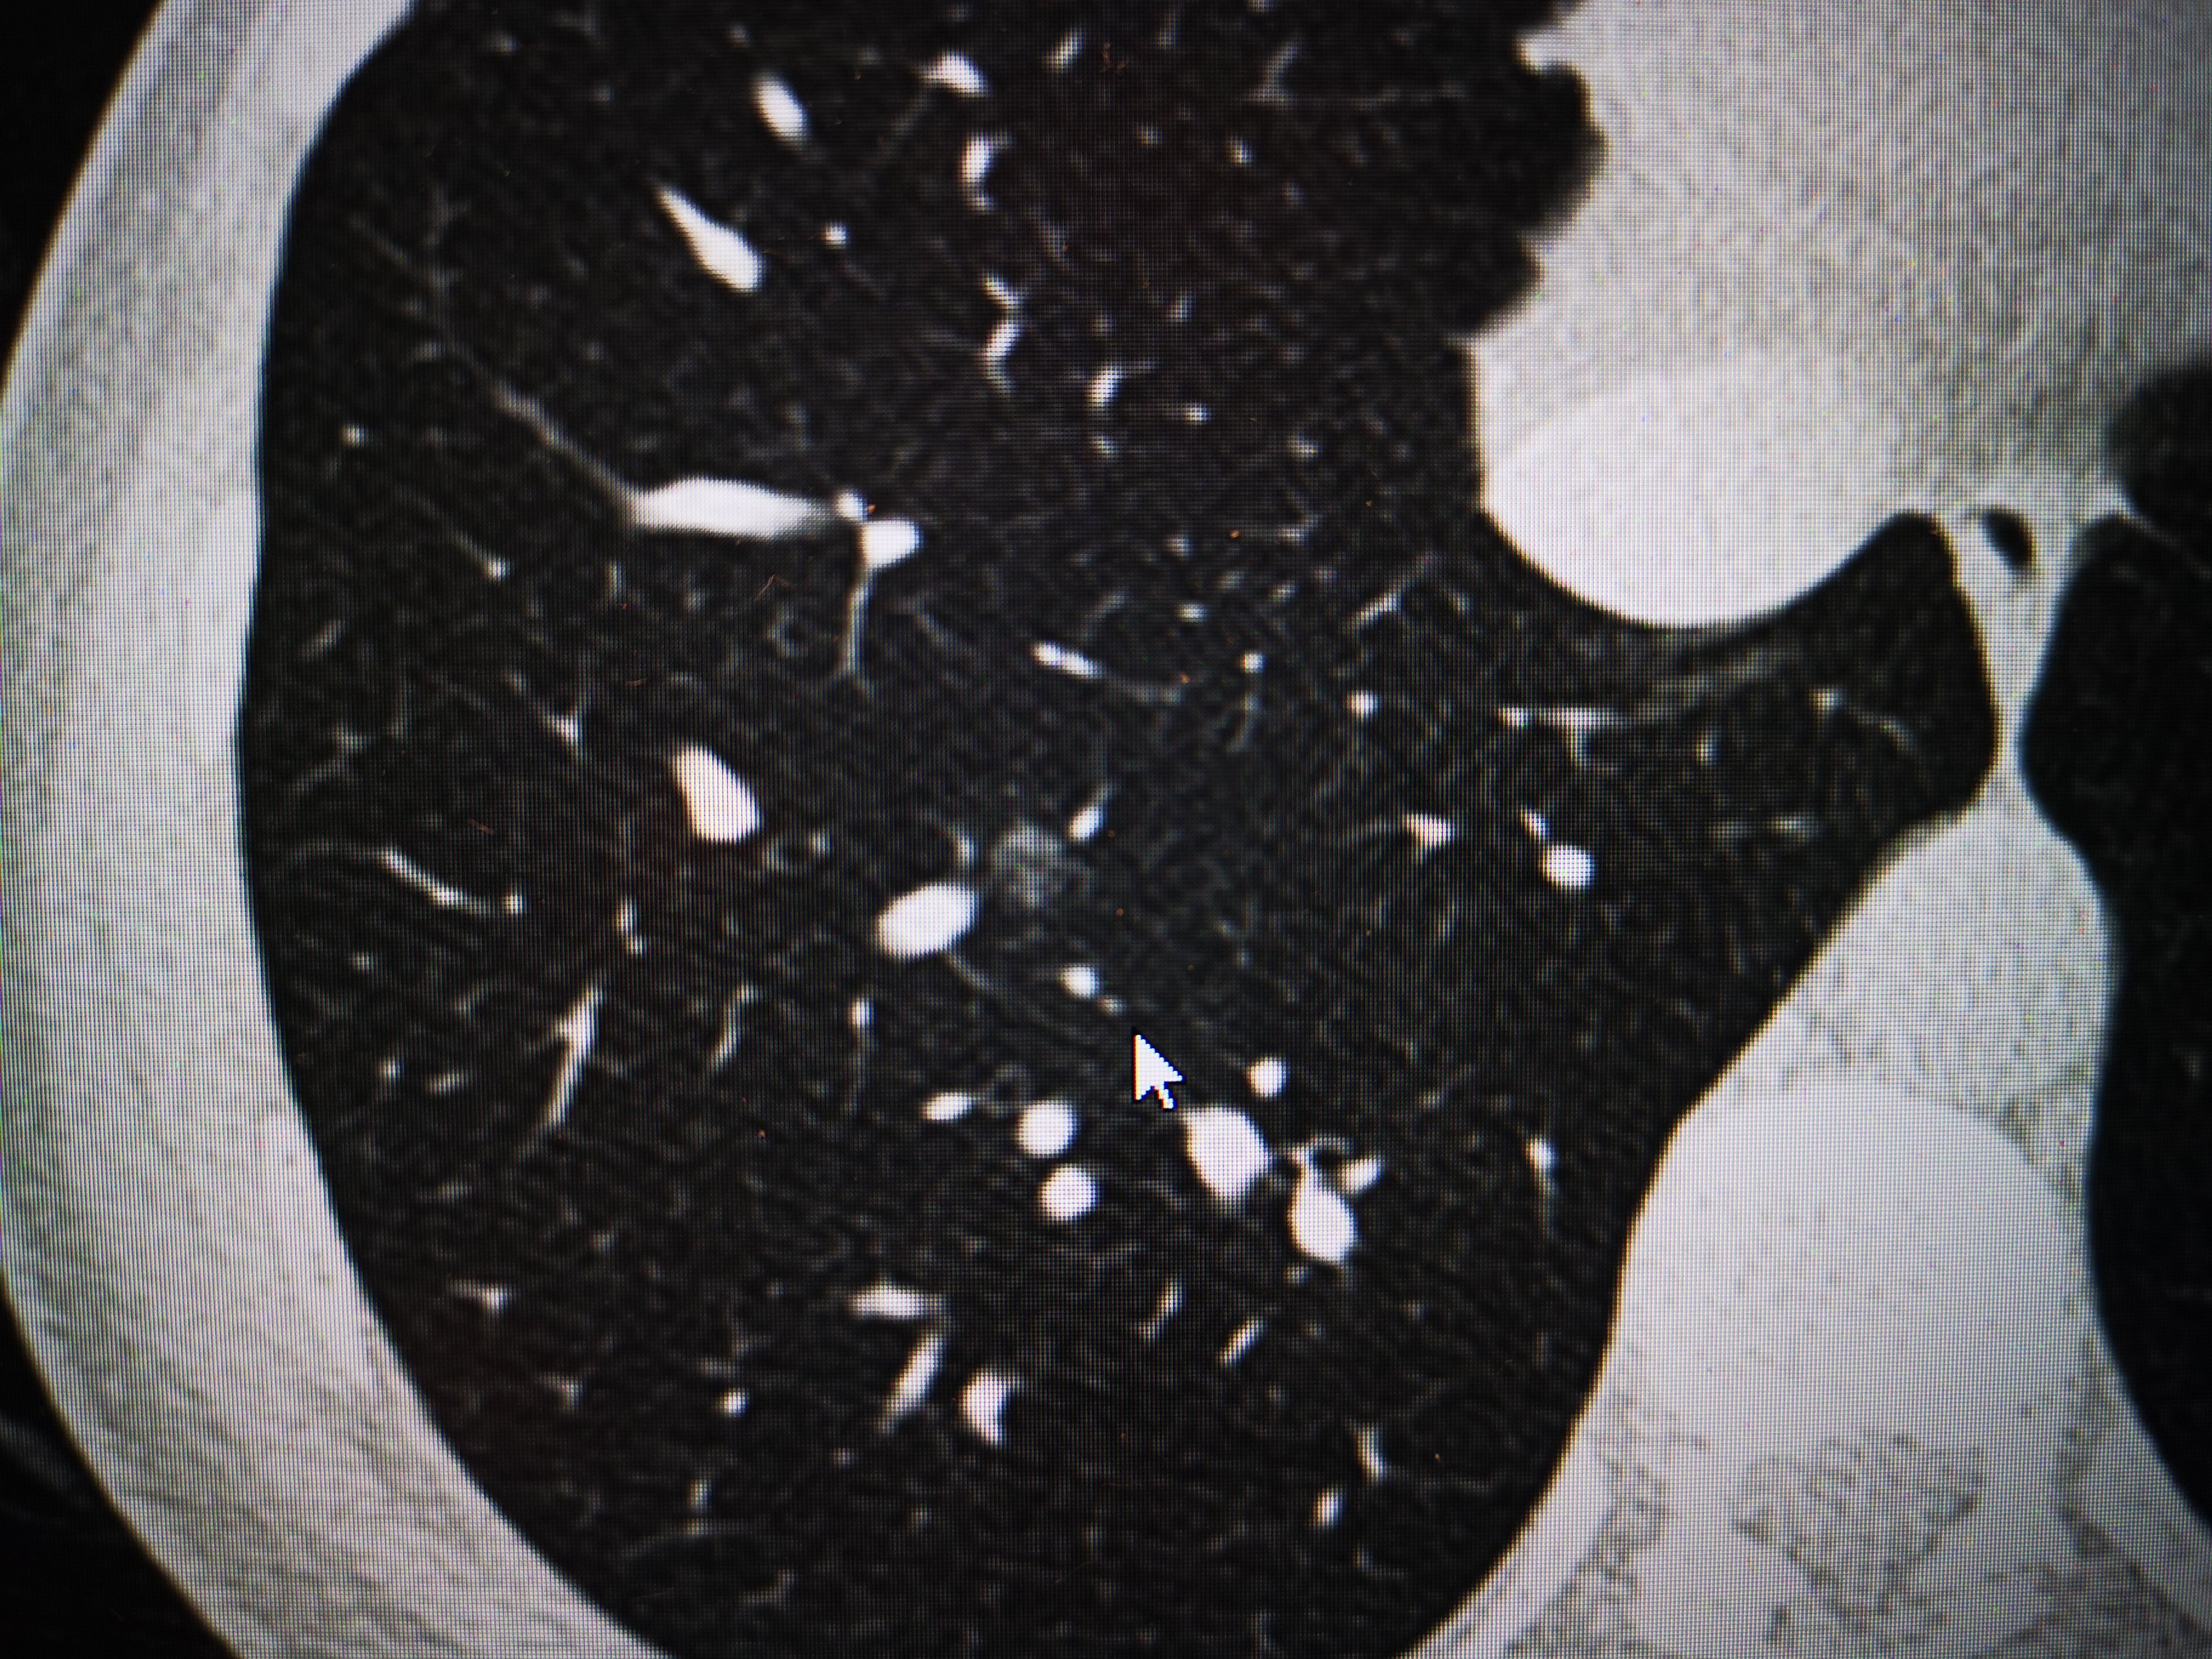

层面一:多发的磨玻璃结节

肺磨玻璃结节长什么样

肺结节/磨玻璃结节经典病例集合,看了你也是专家!持续更新.谢谢关注!